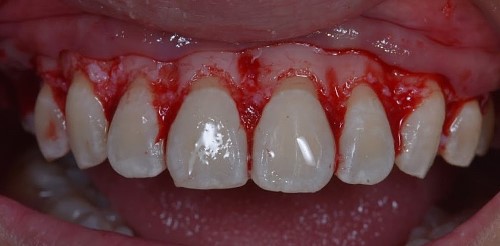

The STL files of the maxilla and teeth were manipulated using BlueSky Plan software (see Fig. 8). Subsequently, a guide was designed to facilitate osseous resection, adapting to both the teeth and the maxilla (see Fig. 9). In the surgical phase, a full-thickness flap was raised in the upper jaw, and the guide was affixed (see Figs 10 and 11). The guide snugly conformed to the bone, and its position was verified with a margin distance from CEJ set at 3 mm (see Figs 12 and 13). Postoperative results at 2 and 12 months are shown in Figs 14 and 15. The final outcomes closely resembled the Digital Smile Design (DSD) simulation conducted before treatment (see Fig. 16).